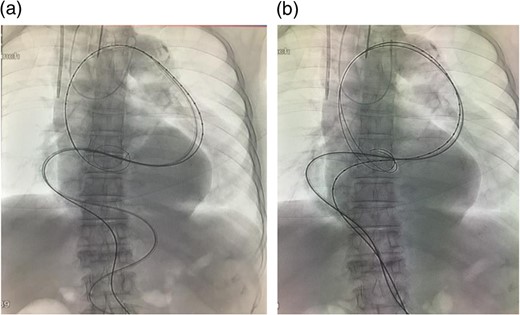

A stiff sheath (Destination®, 6 Fr 90 cm, Terumo, Tokyo) was introduced from the left side. The sheath was placed beyond the aneurysm. Lunderquist® guide wire was introduced through the sheath. The aortic angulation was straightened and the most severe angulation below the aneurysm was reduced (Fig. 2).

(a) A sheath was introduced and the angulation was slightly reduced. (b) A guide wire was introduced through the sheath. The angulation was further reduced by this procedure. In addition, the angulation of the wire (black arrow), which was used to introduce the stent graft main body, was reduced. Thus, the wire was advanced through the aorta where angulation was small.